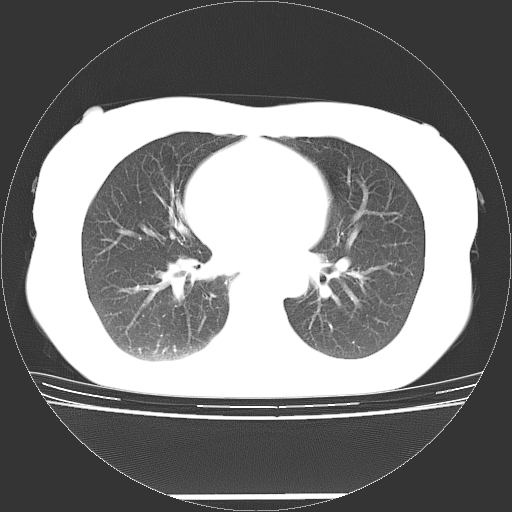

标题: CT27224:女,43岁,体检发现左肺下叶结节影。 [打印本页]

女,43岁,体检发现左肺下叶结节影。

左下肺外带胸膜下见孤立实性均匀密度结节影,边缘光整,增强呈渐进性强化,病灶吴分叶征及毛刺征象;支持硬化性血管瘤。

左肺下叶基底段圆形结节,多考虑:错构瘤>硬化性血瘤>炎症假瘤>周围性肺癌!期待结果!

左肺下叶外侧基底段圆形结节,多考虑:错构瘤>硬化性血瘤>炎症假瘤>周围性肺癌!期待结果!

左肺下叶外基底段良性结节(错构瘤?)。